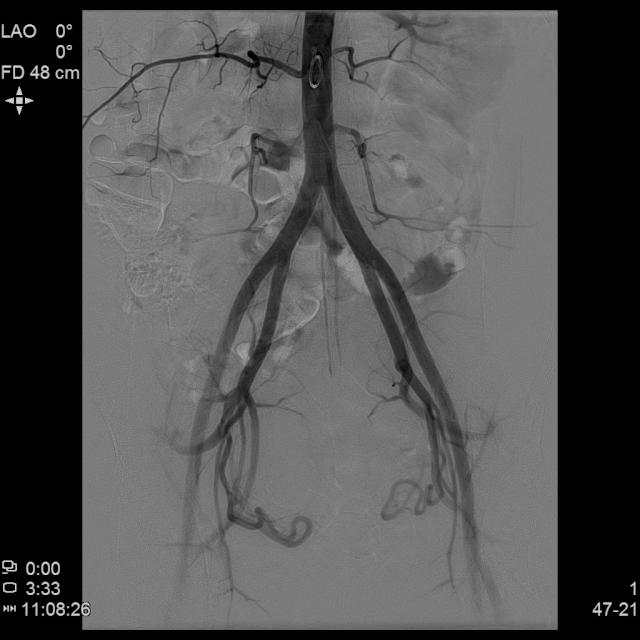

- 经桡动脉入路置入导管造影显示双侧子宫动脉明显增粗,染色丰富,子宫明显增大